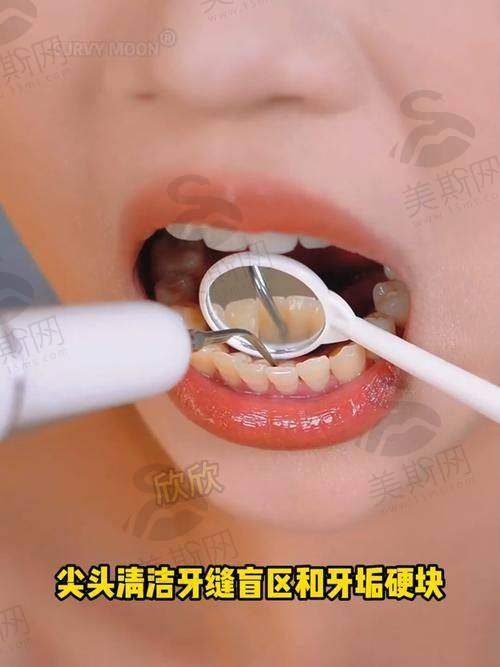

5. 牙周病诊疗中 心:针对牙龈炎、牙周炎开展龈上洁治、龈下刮治、牙周翻瓣术、引导性组织再生术(GTR),采用激光牙周治疗技术,减少出血与疼痛,缩短愈合周期30%。

12. 哈尔滨优诺博士口腔龈上洁治(洗牙):260元/次

13. 哈尔滨优诺博士口腔龈下刮治(单象限):680元